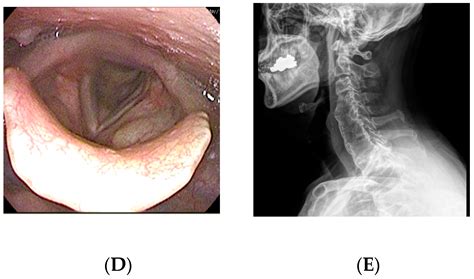

• osteophytes swallowing difficulty

If you suspect that your symptoms are related to bone spurs, a healthcare professional will perform a physical examination to test your reflexes, muscle strength, and range of motion. To confirm the diagnosis of osteophytes in cervical vertebrae, imaging is typically required.

• X-rays: Highly effective at visualizing the bony projections and narrowing of the disc space.

• MRI (Magnetic Resonance Imaging): Provides detailed images of soft tissues, nerves, and the spinal cord, allowing doctors to see if the bone spurs are compressing neural structures.